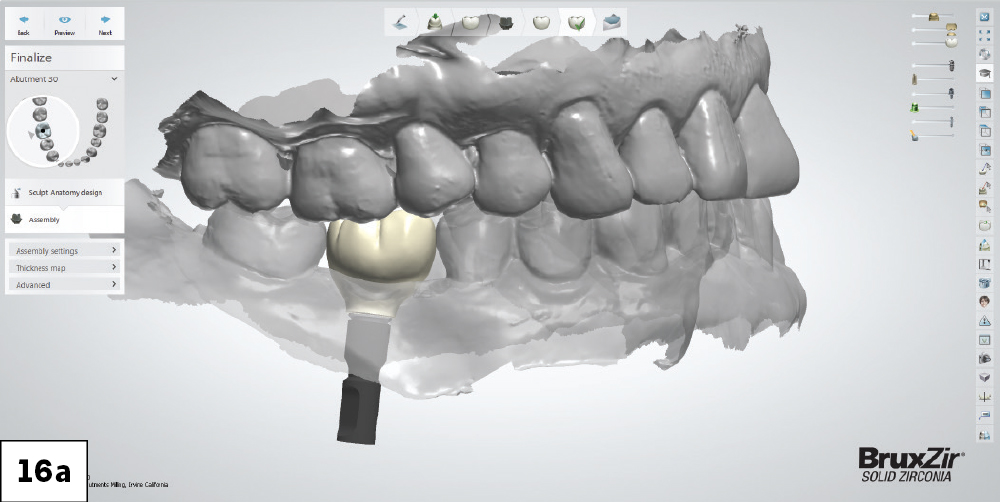

3D Oral Scan Showing Planned BruxZir Implant

Figures 16a, 16b: The laboratory generated a final restoration design, taking into consideration proper contacts and contours for optimal adaptation of the soft tissue to the coronal portion of the screw-retained crown.